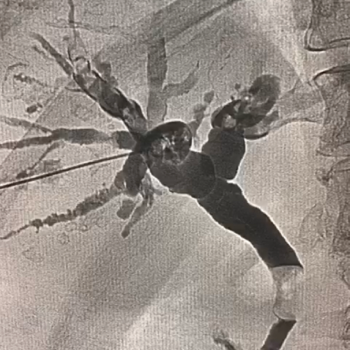

Si tienes cálculos o piedras en la vesícula biliar, debes operarte para evitar complicaciones como colecistitis o inflamación y

dolor de la vesícula, perforación de la vesícula, obstrucción de los conductos biliares por cálculos, pancreatitis y cáncer de vesícula.